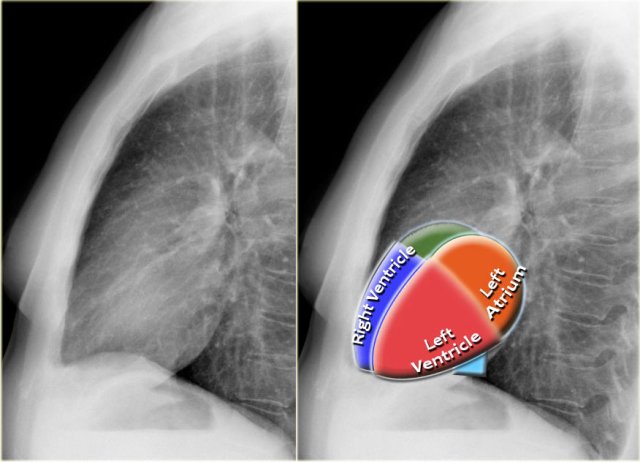

Heart and Pericardium

On a chest film only the outer contours of the heart are seen.

In many cases we can only tell whether the heart figure is normal or enlarged and it will be difficult to say anything about the different heart compartments.

However it can be helpful to know where the different compartments are situated.

Left Atrium

- Most posterior structure.

- Receives blood from the pulmonary veins that run almost horizontally towards the left atrium.

- Left atrial appendage (in purple) can sometimes be seen as a small outpouching just below the pulmonary trunk.

- Enlargement of the left atrium results on the PA-view in outpouching of the upper heart contour on the right and an obtuse angle between the right and left main bronchus. On the lateral view bulging of the upper posterior contour will be seen.

Right Atrium

- Receives blood from the inferior and superior vena cava.

- Enlargement will cause an outpouching of the right heart contour.

Left Ventricle

- Situated to the left and posteriorly to the right ventricle.

- Enlargement will result on the PA-view in an increase of the heart size to the left and on the lateral view in bulging of the lower posterior contour.

Right Ventricle

- Most anterior structure and is situated behind the sternum.

- Enlargement will result on the PA-view in an increase of the heart size to the left and can finally result in the left heart border being formed by the right ventricle.

- The upper posterior border of the heart is formed by the left atrium.

- Enlargement will result in bulging of the upper posterior contour

- Forms the lower posterior border.

- Enlargement will displace the contour more posteriorly.

- The lower retrosternal space is filled by the right ventricle.

- Enlargement of the right ventricle will result in more superior filling of this retrosternal space.